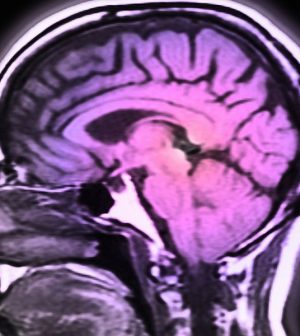

Glioma is a relatively rare, but often fatal, cancer. About 80% of malignant brain tumors are gliomas. They have a five-year relative survival rate of just 5%.